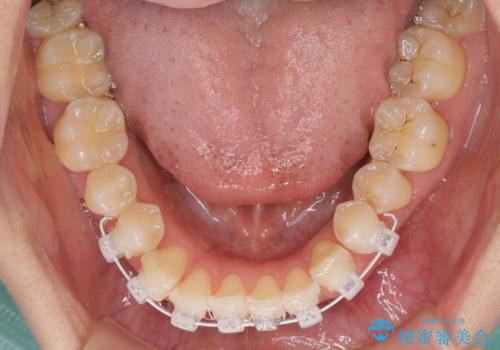

補綴治療に先立ち、下顎前歯の部分矯正を行い、前歯の咬み合わせの安定性向上を図りました。

当初は上顎の補綴治療のみを希望されていましたが、仮歯装着期間に上下の前歯の接触が気になったため、部分矯正を行うこととしました。